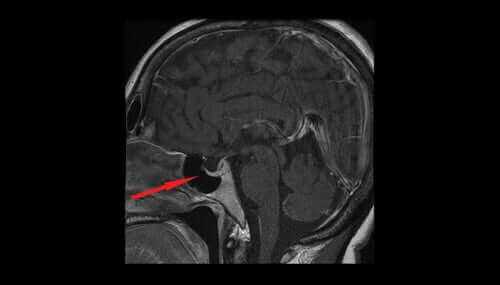

ADH, også kjent som vasopressin eller antidiuretisk hormon, dannes i hypothalamus og lagres i hypofysens baklapp. Derfra går det videre til nevrohypofysen før det ender opp i blodstrømmen. Det bidrar til å regulerer mengden vann i kroppen ved å kontrollere mengden vann nyrene skiller ut. I denne artikkelen skal vi se nærmere på egenskapene og effektene av ADH.

Høye nivåer av dette hormonet fremmer vannretensjon i kroppen via nyrene. Dette er en tilstand kjent som SIADH-syndrom (syndrome of inappropriate secretion of antidiuretic hormone på engelsk).

Hos pasienter som lider av dette syndromet frigjøres overdrevne mengder ADH når de ikke trenger det. Dette resulterer i overdreven vannretensjon som fortynner blodet, som gir en karakteristisk lav saltkonsentrasjon.

Overdrevne nivåer av dette hormonet kan skje som en bivirkning hos visse medisiner, samt sykdommer i lungene, brystveggen, hypothalamus og hypofysen.

Lave nivåer av det antidiuretiske hormonet vil få nyrene til å skille ut overflødig vann. Urinvolumet vil øke, noe som vil føre til dehydrering og en reduksjon av blodtrykket. Lave nivåer av dette hormonet kan indikere en skade på hypothalamus, hypofysen eller primær polydipsi.